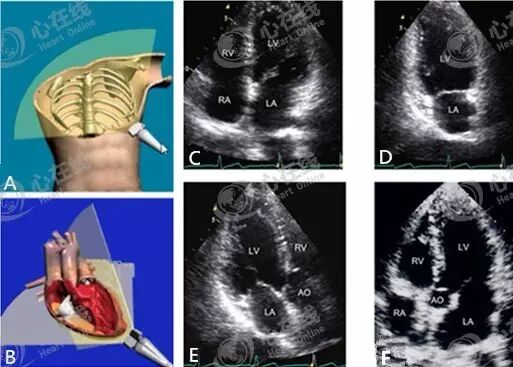

心尖切面就是将超声探头放在心尖波动处,然后旋转、倾斜探头,从而获得心尖部不同方位的切面。图A是人体心尖切面示意图,在此切面基础上逆时针旋转探头(图B),即可获得心尖部的其他切面,如四心腔切面(图C)、两心腔切面(图D)、三心腔切面(图E)、五心腔切面(图F)。